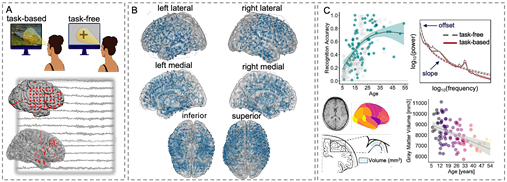

人脑各区域的发育速度不同,许多区域持续发育至成年早期甚至中年。传统研究主要依赖结构影像(如MRI)和头皮脑电(EEG),但前者缺乏时间精度,后者空间分辨率有限,难以揭示脑区特异性的神经生理机制。2025 年 7 月 21 日Zachariah R. Cross在Nature Human Behaviour上发表了一篇题为 “The development of aperiodic neural activity in the human brain” 的文章(IF=15.9)。这项研究通过分析 101 名儿童和成人的颅内脑电图(iEEG)记录结合视觉记忆任务(任务态)与静息态数据。绘制了非周期(1/f 类似)活动的发育轨迹,揭示了大脑发育过程中的神经生理学机制,为理解大脑如何支持注意力和记忆容量的发育提供了新的视角。

研究团队纳入101名5–54岁癫痫患者(iEEG监测),采集5691通道的颅内脑电,结合视觉记忆任务(任务态)与静息态数据。采用IRASA算法提取1–60 Hz非周期性斜率/偏移,映射至Desikan-Killiany-Tourville脑区;线性/非线性混合效应模型分析年龄-脑区-任务状态交互作用,并关联灰质体积与记忆行为,控制发作灶与伪迹。通过非周期活动的斜率和偏移量来衡量神经元群体的兴奋与抑制平衡,斜率越陡峭表明抑制信号越强,反之则表明兴奋信号占主导。研究还结合了结构性成像措施,分析了灰质体积与非周期活动之间的关联。

图1. 实验设计、电极覆盖情况与关键变量

图2. 非周期成分的斜率与截距在不同脑区的差异及其与灰质体积(GMV)的相关性